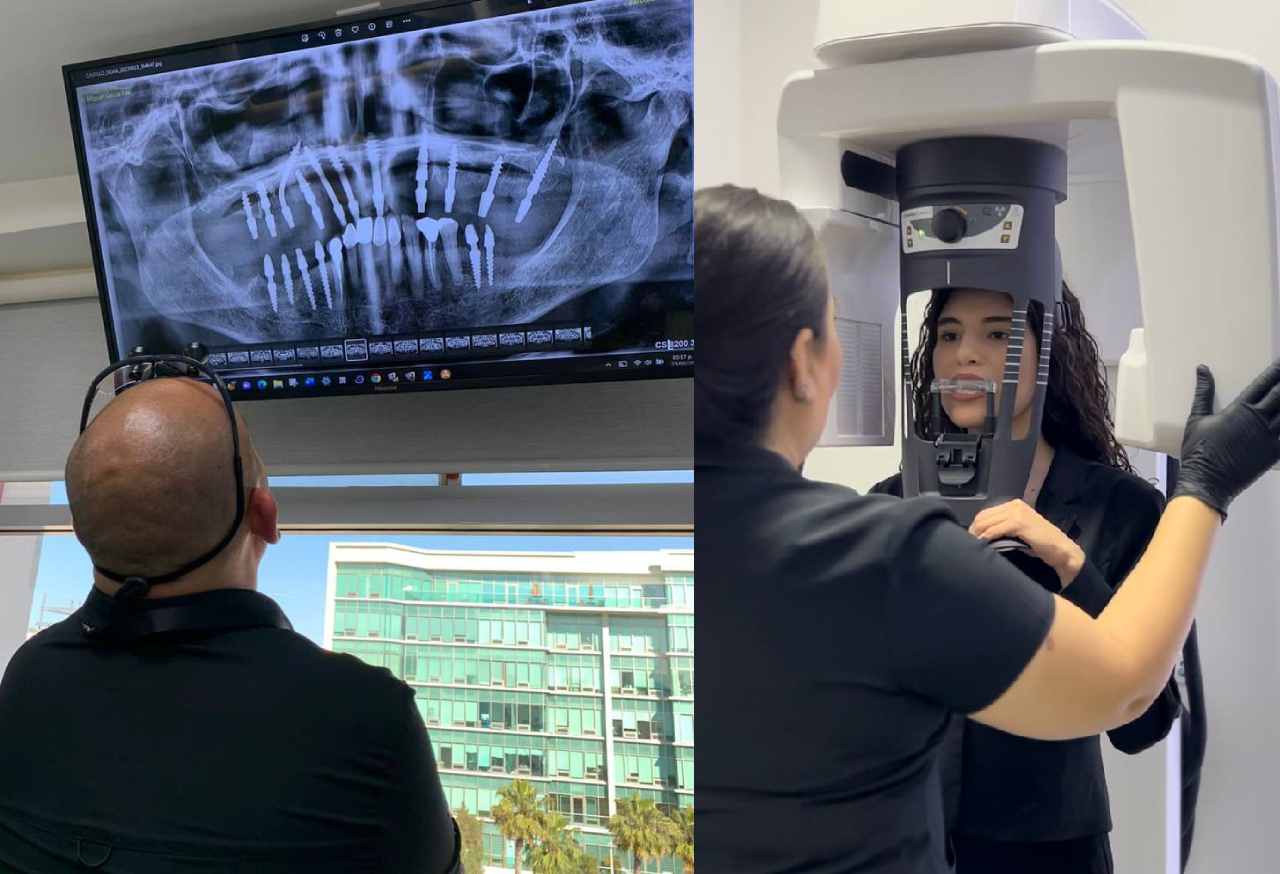

Cutting-Edge Technology

We utilize the latest advancements in dental technology and techniques to ensure your treatment is efficient, precise, and minimally invasive. Our state-of-the-art facility and our In-house lab is equipped with the tools necessary to provide you with the best care possible.

✅ Complete diagnostics & personalized planning (CBCT + records)

At Dr. Yee’s clinic inside Full Arch Baja / Baja Oral Center, patients receive world-class dental care in a state-of-the-art environment. Our in-house digital lab and advanced equipment allow us to deliver faster, more precise results—all under one roof.

We’ve also added a dedicated CBCT Center, offering high-resolution 3D imaging to ensure accurate diagnosis and treatment planning from the very first visit.